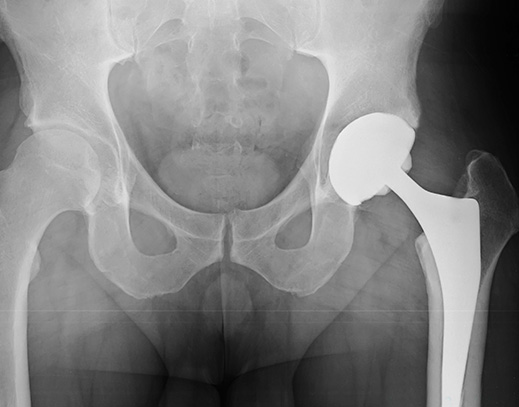

Since 2013, the FDA has warned that metal-on-metal hips pose “unique risks.” The metal cup and ball can rub against each other, causing pain and releasing metal particles into the surrounding bone and soft tissue. Continuing erosion of the hip implant may eventually cause the device to fail. In many cases, patients have been required to undergo painful revision surgery to remove the defective metal-on-metal hip implant and replace it with a different system.